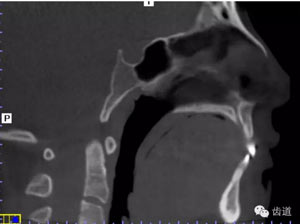

治療后氣道截圖(CBCT)